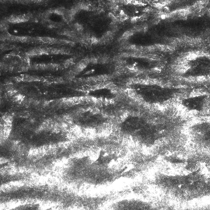

Dermoscopy image

This is a collision tumour in which a melanoma in situ and a solar lentigo are both occurring in the same lesion.

These two diagnoses are different and separate, and this case demonstrates that if a partial sample biopsy is taken, you may miss the other diagnosis.